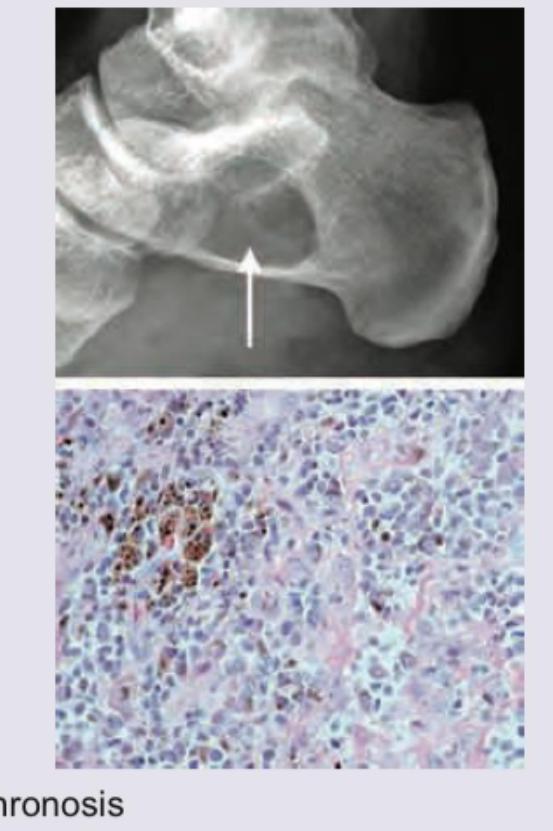

Question 5: Identify the lesion in a 20-year-old male whose foot X-ray is shown below:

- A. Ochronosis

- B. Haemophilic pseudo-tumour

- C. Pigmented villonodular synovitis

- D. Mycetoma (Correct Answer)

Explanation: ***Mycetoma*** - The X-ray image shows a **lytic lesion** with surrounding sclerosis in the calcaneus, indicated by the arrow, which is characteristic of **mycetoma**. The histological image reveals an inflammatory infiltrate with **pigmented fungal grains (brown aggregates)**, confirming the diagnosis. - Mycetoma is a chronic granulomatous infection of subcutaneous tissues, often extending to bone, particularly in the foot. Its characteristic features include **grains (colonies of microorganisms)** within the lesions. *Ochronosis* - Ochronosis would show **dark discoloration of cartilage** and connective tissues due to **homogentisic acid** deposition, leading to degenerative arthritis. This would appear on X-ray as **calcification of cartilage** (e.g., intervertebral discs, menisci) rather than focal lytic lesions with grains. - The histological image would show characteristic **ochre-colored pigment deposits**, not fungal grains. *Haemophilic pseudo-tumour* - A haemophilic pseudo-tumour is a rare complication of hemophilia, often presenting as a **large, expanding lesion** within bone or soft tissue, typically due to recurrent hemorrhage. - X-rays would reveal a **well-defined, expansile lesion** with cortical thinning or bone destruction, and histology would show features of chronic hemorrhage, fibrous tissue, and hemosiderin deposition, not fungal grains. *Pigmented villonodular synovitis* - This condition involves **proliferation of synovial tissue**, often affecting large joints like the knee or hip, leading to bone erosions and cysts. - Histology would show **hyperplastic synovium** with hemosiderin deposition, multinucleated giant cells, and lipid-laden macrophages, but not fungal grains as seen in the microscopy image.